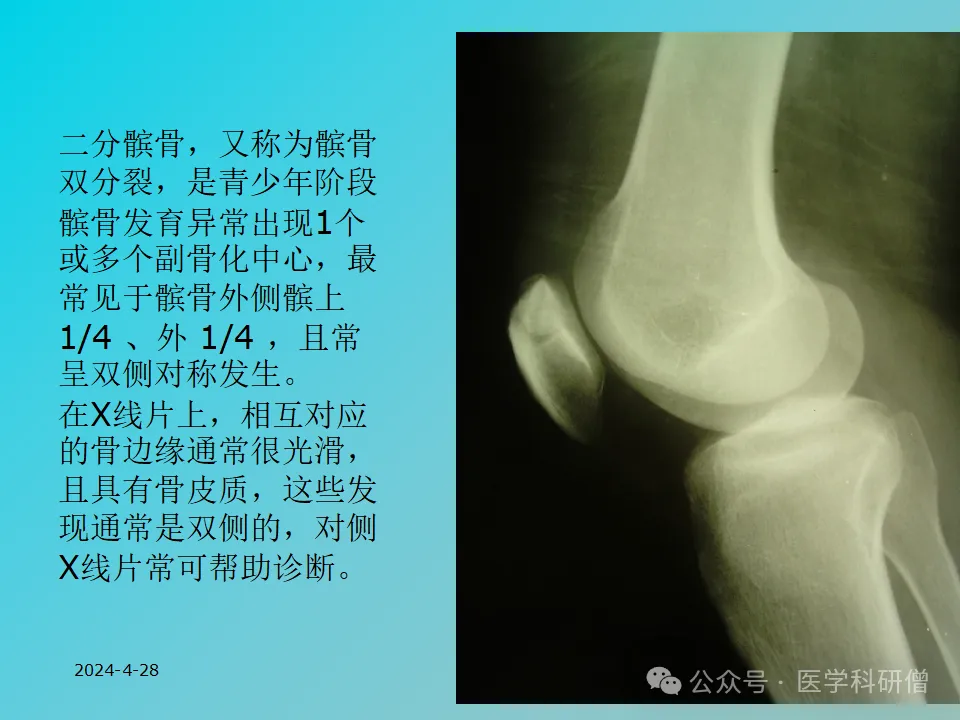

虽然文档中没有详细说明骨折的分类,但值得一提的是,二分髌骨作为一种发育异常,有时可能会被误诊为髌骨骨折。二分髌骨实际上是髌骨在发育过程中出现的副骨化中心,需要与真正的骨折进行鉴别。